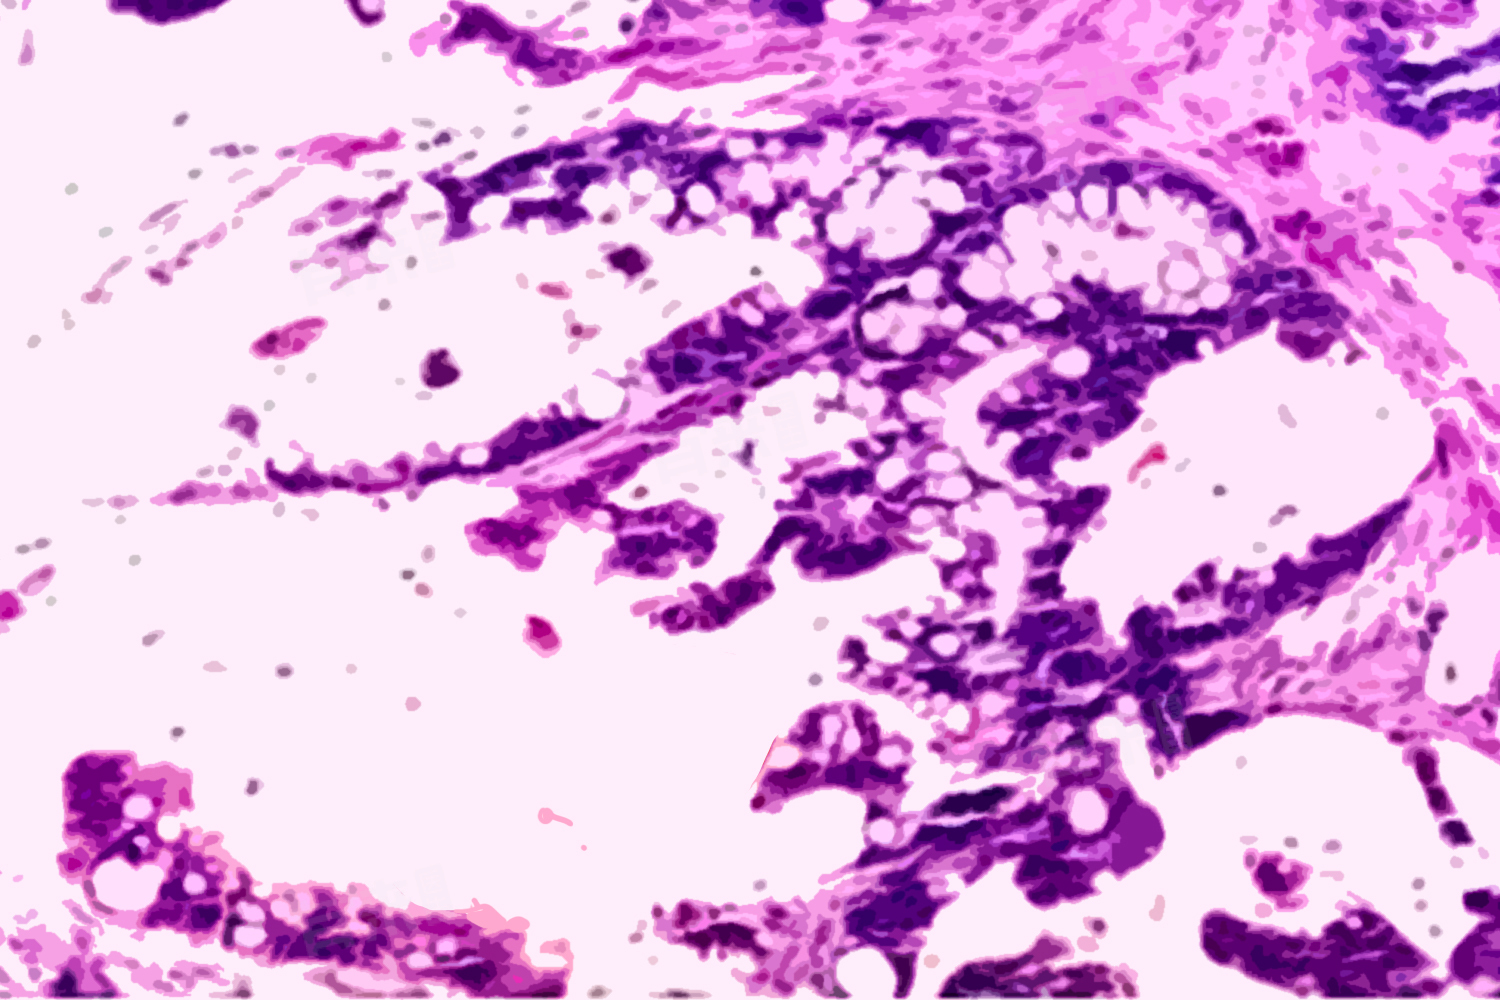

- 粘液性腺癌是腺癌的一种亚型,其特点在于肿瘤细胞能够产生并分泌大量的黏液。肿瘤组织常呈现黏稠或粘液状外观,可以是实性肿块或囊肿样病变。此外,粘液性腺癌的病理学特点还包括肿瘤细胞核的异型性和高度分化。

- 粘液性腺癌的诊断通常依赖于组织活检和病理学检查。通过这些检查,医生可以确认肿瘤的类型、分期以及是否存在转移。